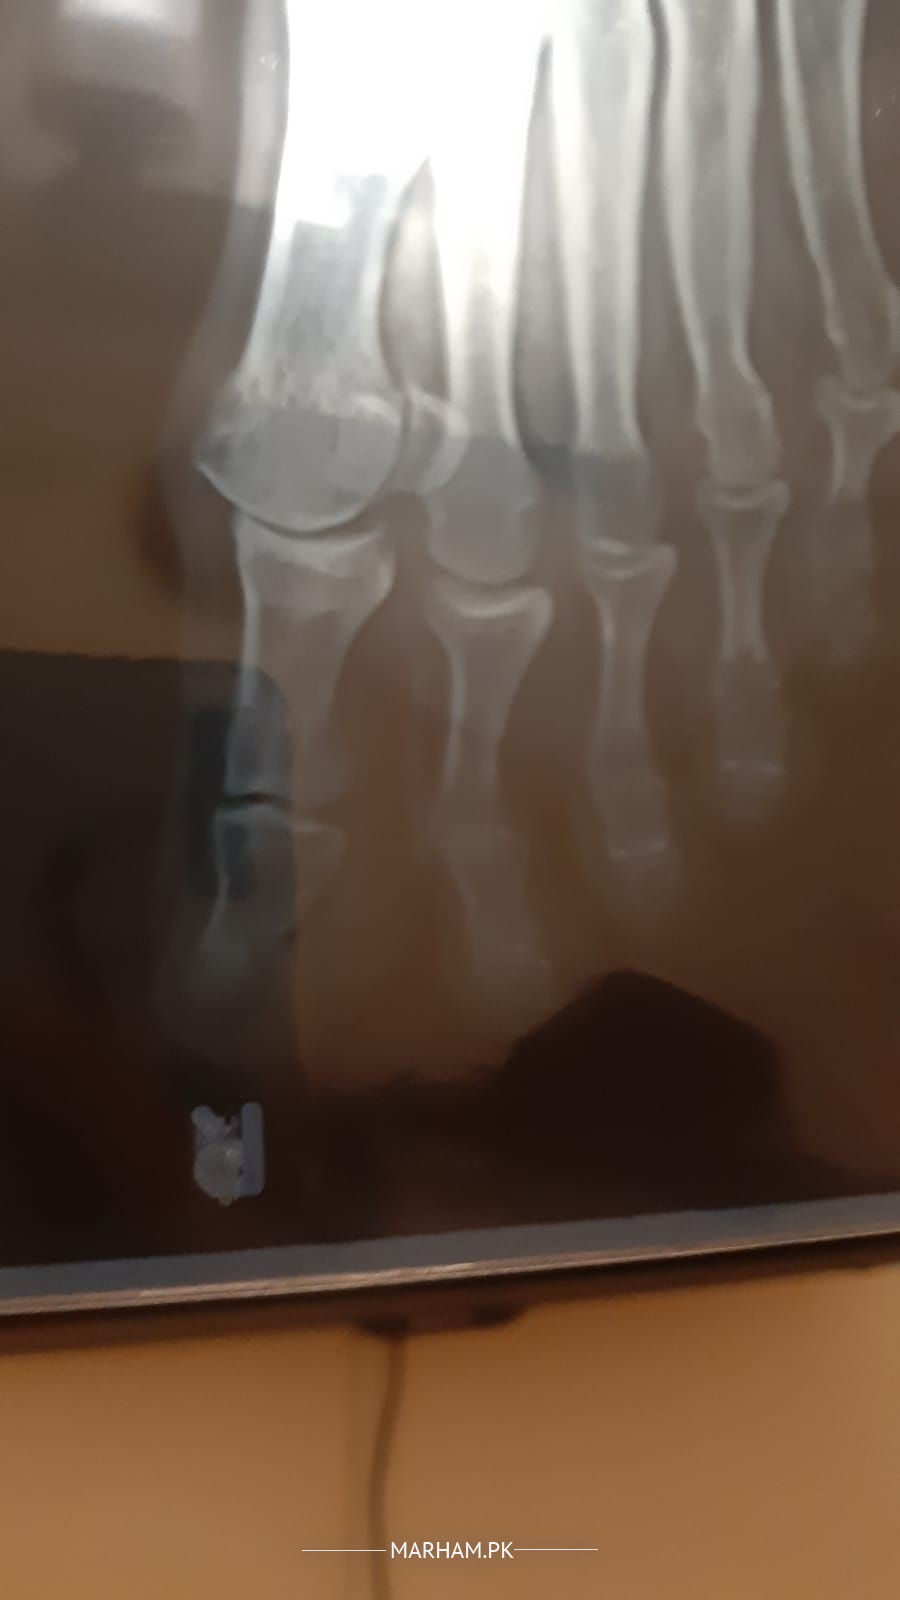

meri ami k paon k anghothay ki haddi barh gyi hai 6 months se treatment chal rha hai laikin woh worst se worst horhi hai I am attaching x-rays please check and consult me k kia krna chahiye. unko bht dard hai.

Assalam o Alaikum. After workup, surgery seems to be the only option ma'am. Barrhi hui haddi trim karnay kay liyay.

She has arthritis and I can sort it out with simple non surgical means make an appointment to see me on 042-32591427,